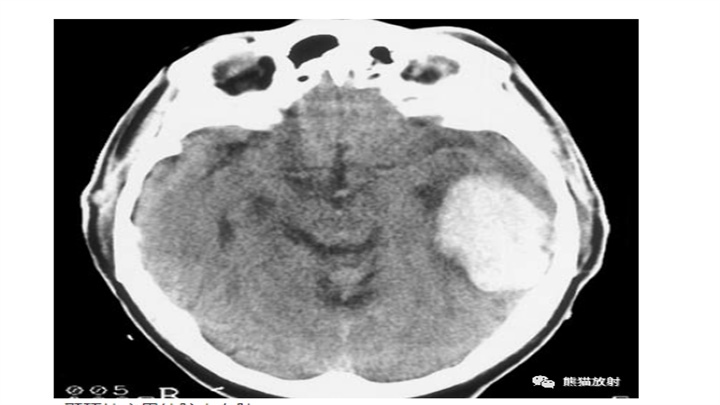

左侧小脑半球血肿。第四脑室变形、移位。

8岁女孩突然昏迷。小脑IPH伴蛛网膜下腔出血,脑干缺血性密度减低,脑积水(侧脑室颞角扩大)。小脑蚓部是“隐性血管瘤”最常见的部位之一。